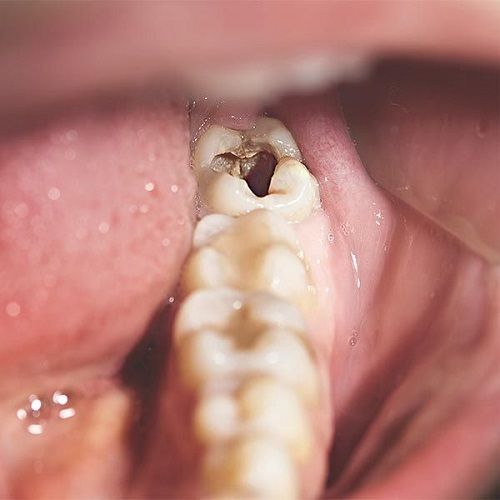

Dấu Hiệu Nhận Biết Răng Khôn Bị Sâu

• Bị đau nhức âm ỉ, hoặc dữ dội ở vùng răng hàm trong cùng.

• Sưng đỏ và viêm nướu quanh răng khôn.

• Hơi thở có mùi hôi và có vị đắng trong miệng.

• Sốt nhẹ, đau lan sang vùng tai hoặc thái dương trong trường hợp nặng.

• Có thể nhìn thấy lỗ sâu nhỏ màu đen, hay nâu trên bề mặt răng.